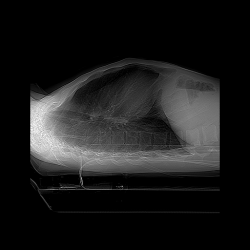

Сделали сыну (18 лет) КТ органов грудной клетки, патологий в легких не нашли, но в заключение написали:

В видимых зонах верхних отделах брюшной полости и забрюшинного пространства в области чревного ствола отмечается гиподенсивное образование толщиной слоя до 12 мм.

Подскажите, пожалуйста, где образование располагается, это в каком то органе или просто в ткани? Видите ли Вы образование на снимках? Может ли это быть ошибочное заключение? Что значит толщиной слоя: видна только толщина, а длина не видна? На что больше похоже образование? Если нужно могу выложить дополнительные снимки.